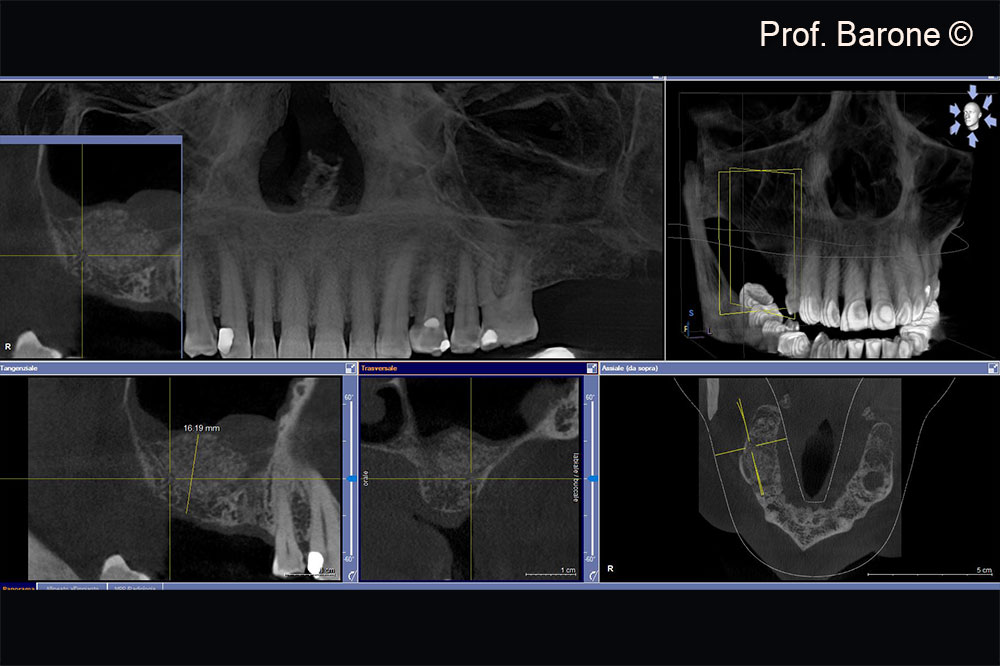

Residual ridge height doesn’t allow implant placement

Residual ridge height doesn’t allow implant placement, sinus membrane hypertrophy